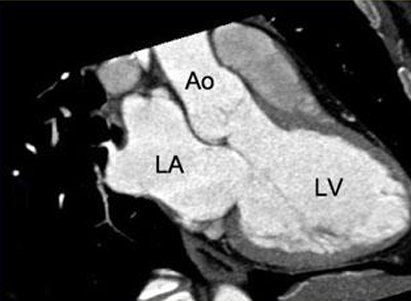

Cardiac CT Scan

Also known as Coronary CT Angiography (CCTA)

Coronary CT Angiography (CCTA)

Cardiac CT Scan (9)

4 chamber view

Cardiac MRI- Cardiac Axes

3 chamber view